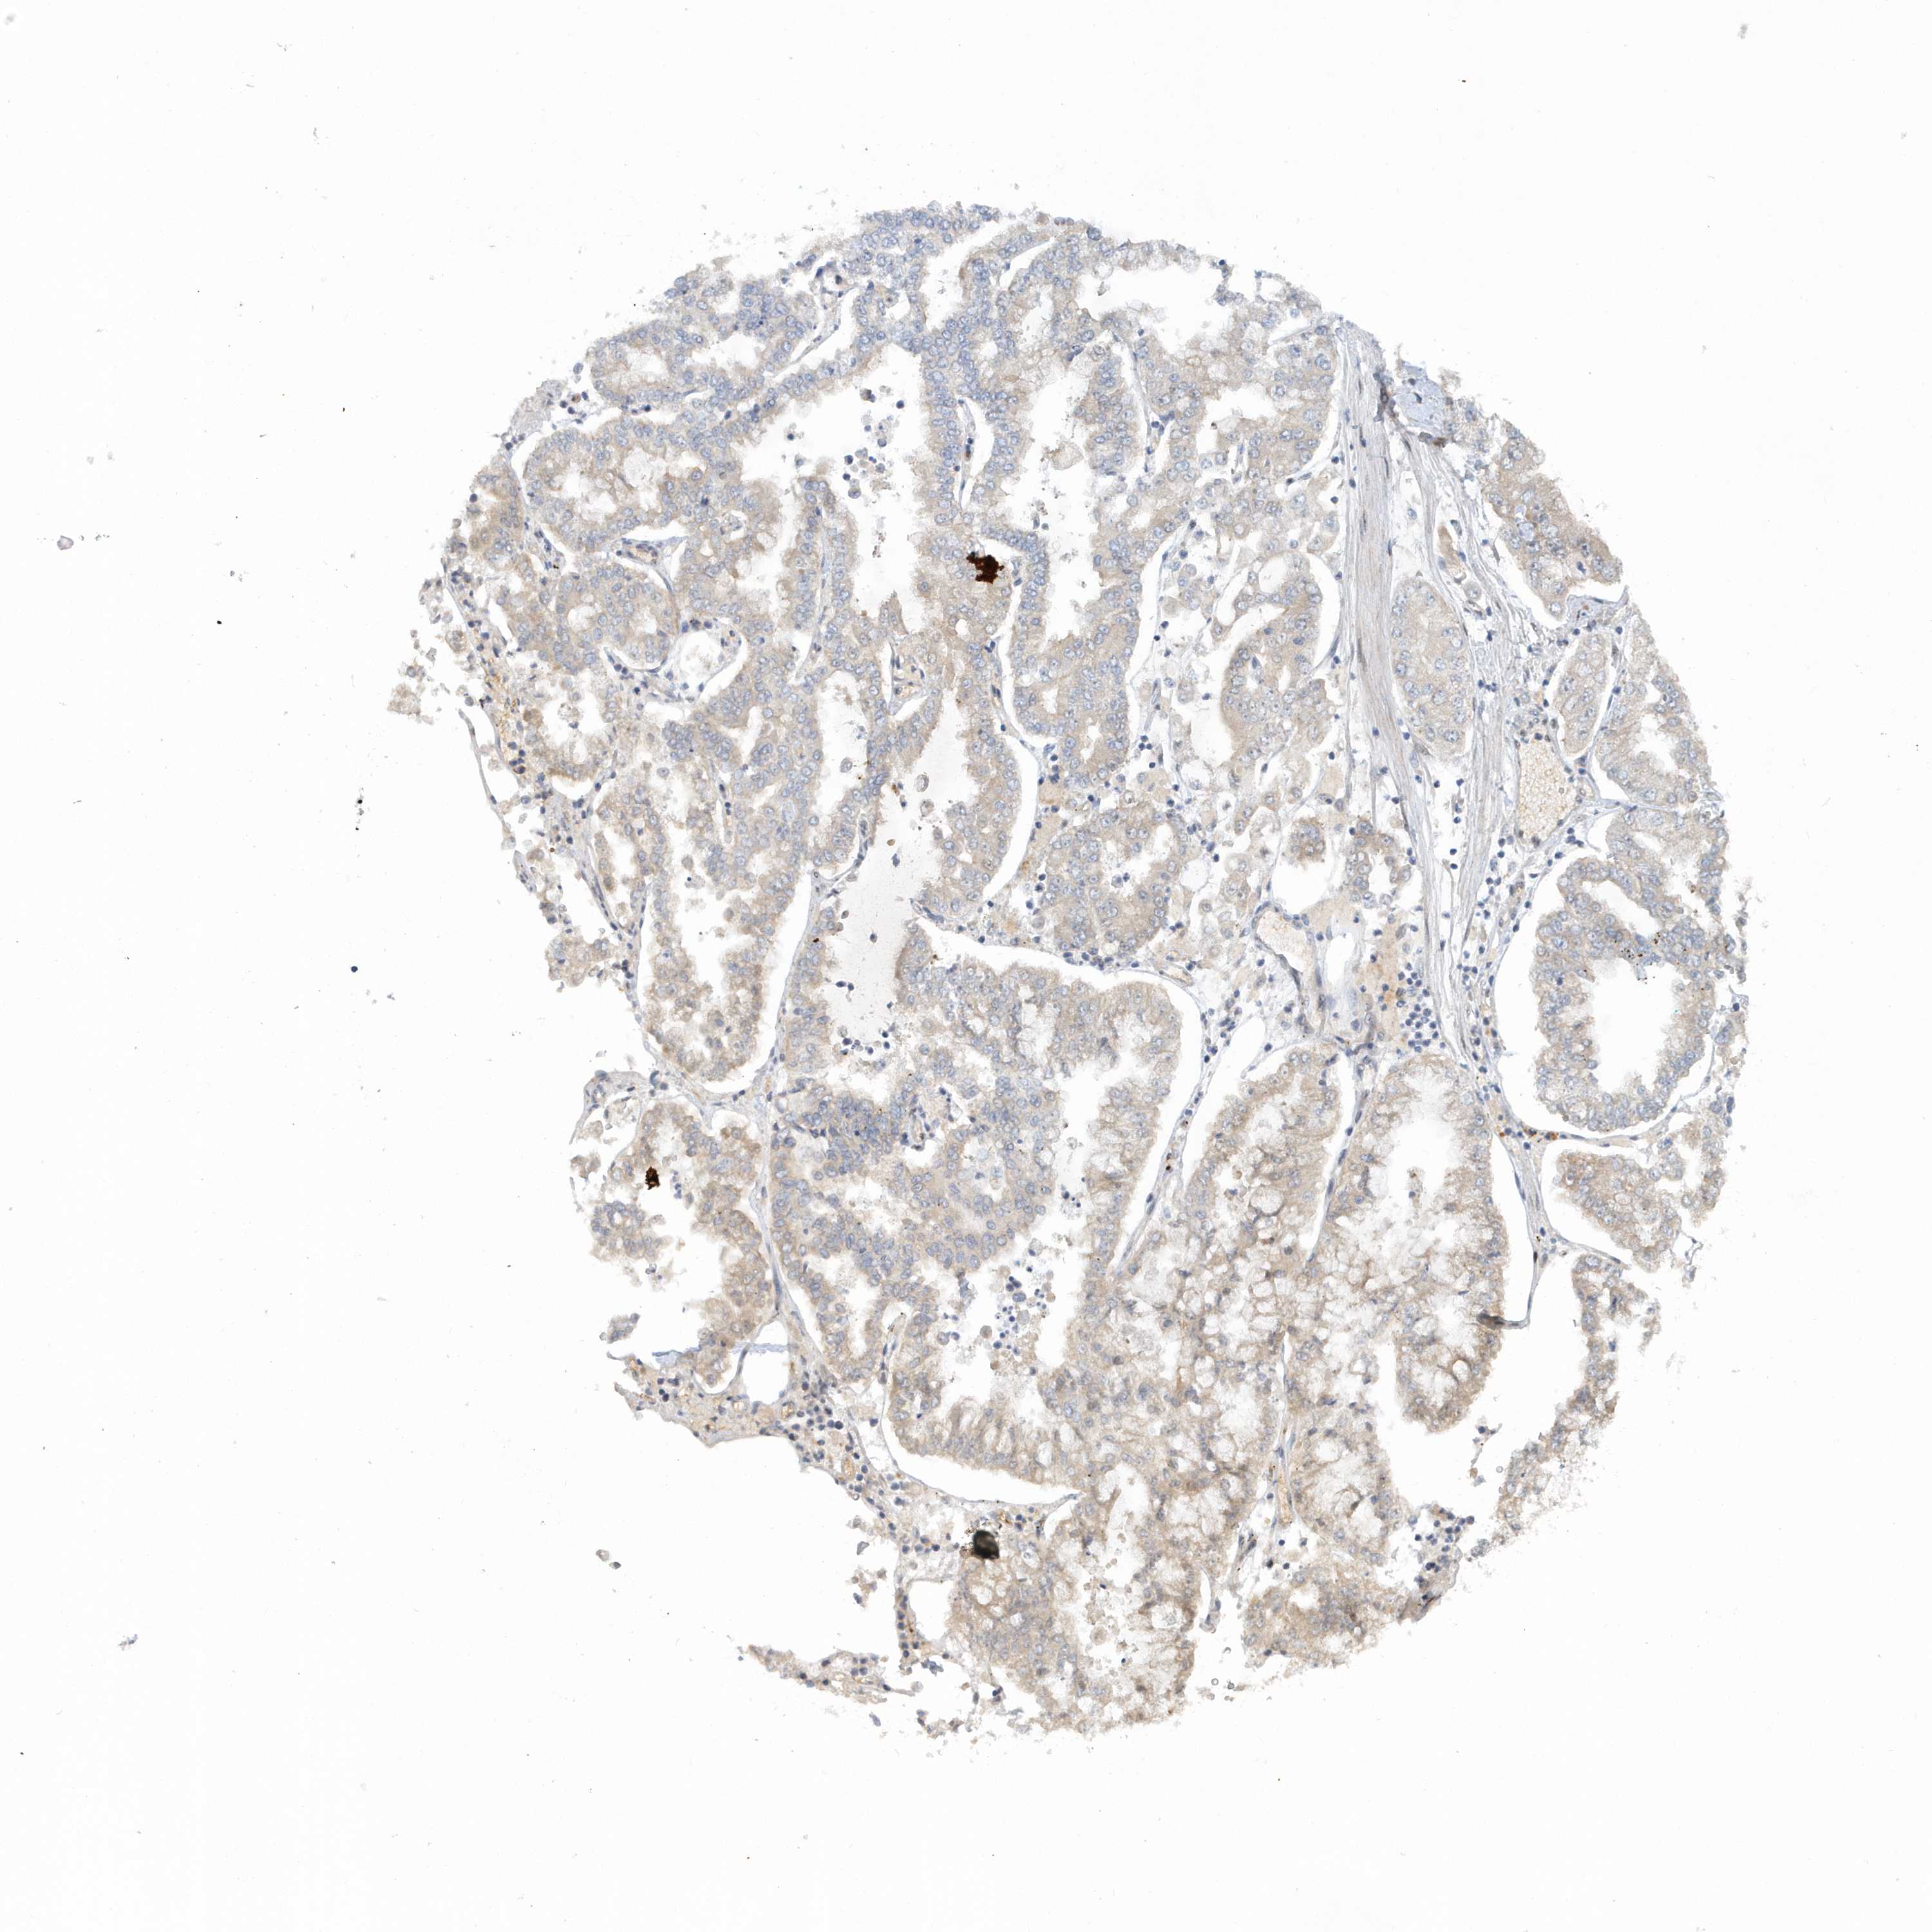

STOMACH CANCER - Protein expressioni

A mouse-over function shows sample information and annotation data. Click on an image to view it in a full screen mode. Samples can be filtered based on level of antibody staining by selecting one or several of the following categories: high, medium, low and not detected. The assay and annotation is described here.

Antibody stainingi

Antibody staining in the annotated cell types in the current human tissue is reported as not detected, low, medium, or high, based on conventional immunohistochemistry profiling in selected tissues. This score is based on the combination of the staining intensity and fraction of stained cells.

Each image is clickable and will lead to virtual microscopy that enables deeper exploration of all samples and also displays staining intensity scores, fraction scores and subcellular localization as well as patient and tissue information for each sample.

Antibody HPA036374

Staining

High

Medium

Low

Not detected

Intensity

Strong

Moderate

Weak

Negative

Quantity

>75%

75%-25%

<25%

None

Location

Nuclear

Cytoplasmic/membranous

Cytoplasmic/membranous,nuclear

Adenocarcinoma, NOS